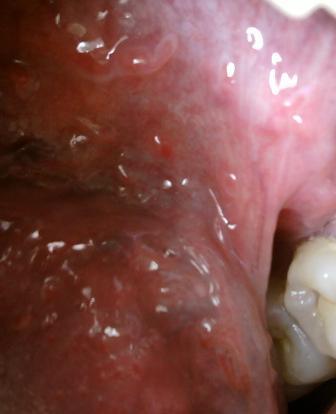

石家庄九州皮肤病医院 > 尖锐湿疣 > > > 初期尖锐湿疣应该怎么治疗尖锐湿疣是日常生活中比较常见的性病,属于皮肤性病的范畴,患病之后希望大家应该引起重视,及时就诊对于疾病的治疗和康复是很关键的,初期是治疗疾病的关键时期,所以在这里希望大家应该了解。不要因为任何原因而不及时治疗,这样只会导致疾病越来越严重,并且最终失去治疗疾病的最佳时机。

中医认为血瘀滞证是由于毒邪结聚日久,阻滞气机,致气血瘀阻所致,尖锐湿疣是一种传染性很强的疾病,其中最为主要的传播途径就是发生不洁性行为。尖锐湿疣病情恶化之后会严重影响患者的健康。一旦患病要及时就医,同时也要注意保持良好的生活习惯,抵制性乱。